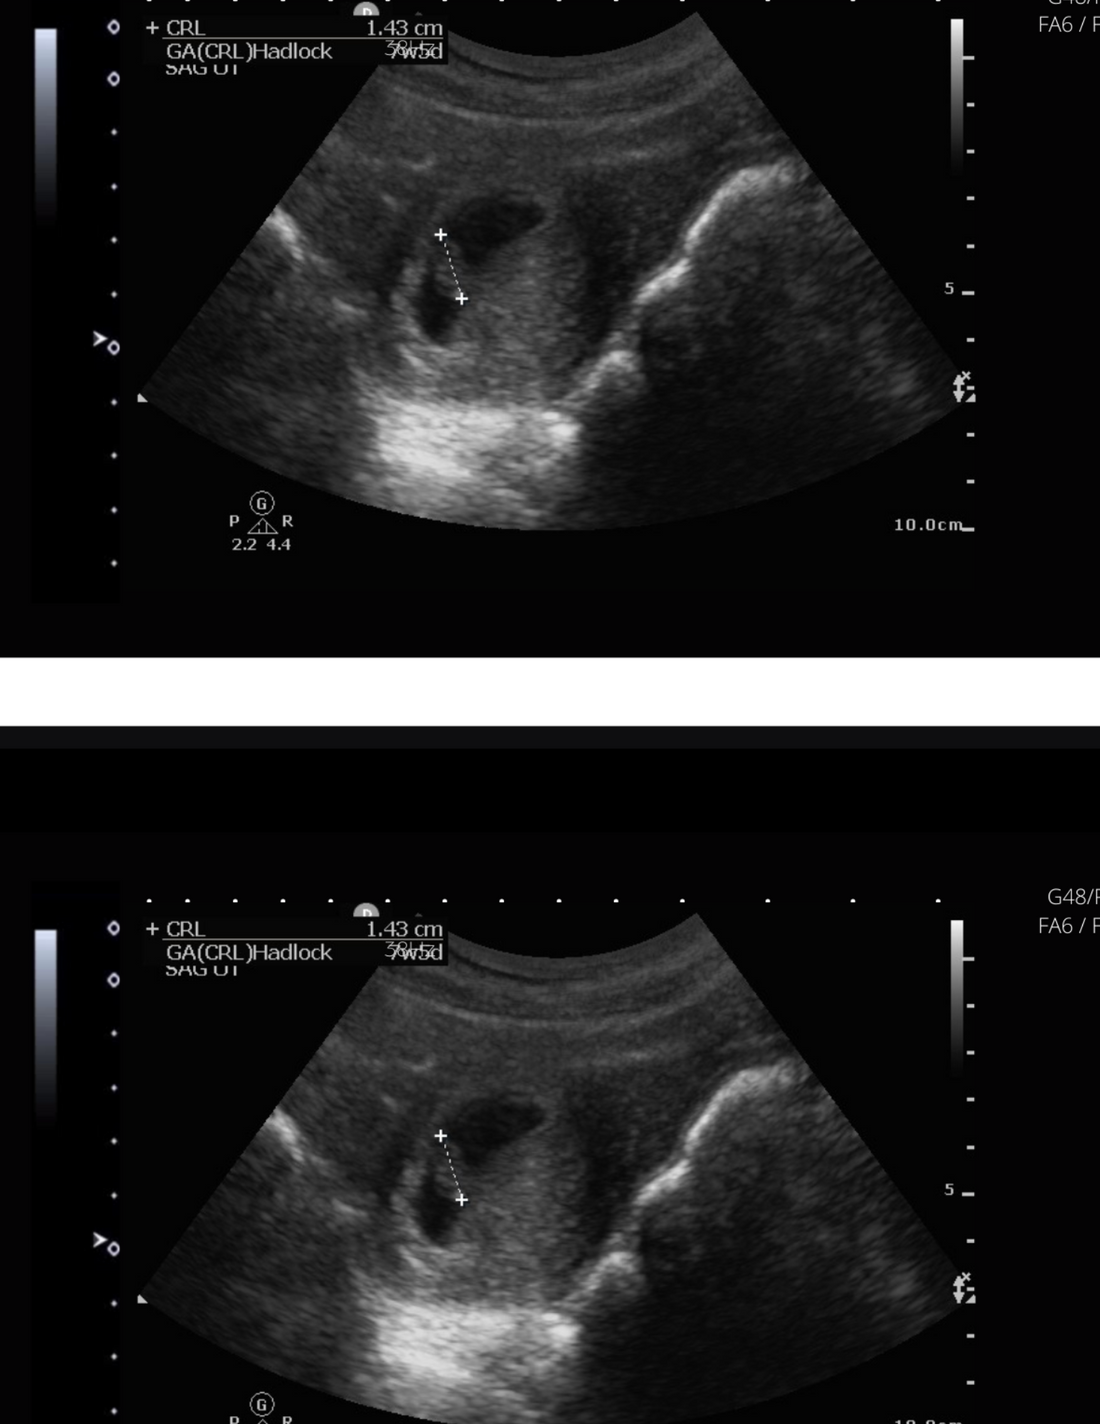

Understanding 5-Week Ultrasound Pictures

During your 5-week ultrasound, the images may not look like much, but remember, your baby is still in the early stages of development. The ultrasound will help your healthcare provider assess the progress of your pregnancy and ensure that everything is on track.